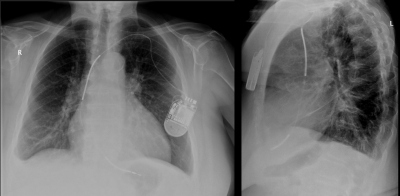

Představujeme kazuistiku 74leté pacientky s primární diagnózou dilatační kardiomyopatie. V rámci došetření byla provedena také invazivní koronární angiografie, která neprokázala významné aterosklerotické postižení koronárních tepen. Echokardiografickybyla zjištěna systolická dysfunkce levé komory (LK) s ejekční frakcí levé komory (EFLK) 30 %,dále bez detekce poruch kinetiky myokardu nebo chlopenních vad. Dysfunkce LK trvala i po více než třech měsících plné farmakoterapie srdečního selhání v maximálních pacientkou tolerovaných dávkách léků. Proto v indikaci primární prevence náhlé srdeční smrti dle platných doporučení Evropské kardiologické společnosti7byl pacientce implantovánjednodutinovýimplantabilníkardioverter-defibrilátor (ICD). V lokální anestezii byla zavedena cestou levé podklíčkové žíly punkční metodou dle Seldingeradefibrilační komorová elektroda Durata 7120Q (St. JudeMedical, USA) do oblasti distálního mezikomorového septa pravé komory. Parametry byly příznivé: senzing vlny R 12 mV, stimulační práh 0,5 V, odpor elektrody 680 ohmů a defibrilační odpor 70 ohmů. Poloha elektrody byla opakovaně skiaskopicky kontrolována,včetně manévrů na stabilitu,a snímky byly archivoványelektronicky. Na elektrody byl následně napojen přístroj FortifyAssura VR (St. JudeMedical, USA).Výkon proběhl bez komplikací, stejně tak i pooperační období. Druhý den byla dle standardního postupu provedena kontrola funkce přístroje. Defibrilační systém fungoval bez problémů s optimálními elektrickými parametry elektrody (senzing vlny R 11 mV, stimulační práh 0,5 V, odpor elektrody 590 ohmů, defibrilační odpor 44 ohmů). Antitachykardické terapie byly naprogramoványve dvou zónách (zóna VT nad 160/min s léčbou 4×antitachykardické stimulace a následně defibrilační výboje, zóna VF nad 200/min s léčbou antitachykardickou stimulací během nabíjení ICD a následně defibrilační výboje). Třetí pooperační den byl proveden pooperační rtg snímek hrudníku v předozadní a boční projekci vestoje (obr. 1), na kterém byla poloha elektrody stacionární ve zvyklé pozici. Pacientka byla propuštěna do domácí péče.

Obr. 1 – Rentgenový snímek po primoimplantaci ICD. Defibrilační elektroda je ve zvyklé pozici v pravé srdeční komoře.Po měsíci od výkonu se pacientka dostavila mimo plánovanou kontrolu pro výboje z ICD při vědomí. Po interogaci přístroje bylo zjištěnoneadekvátní podání výbojů z ICD při flutteru síní s tachykardií spadající do zóny terapie ICD. Pacientka byla zaléčena farmakologicky a byla provedena úprava nastavení parametrů ICD. Dále se neadekvátní terapie již neopakovaly.